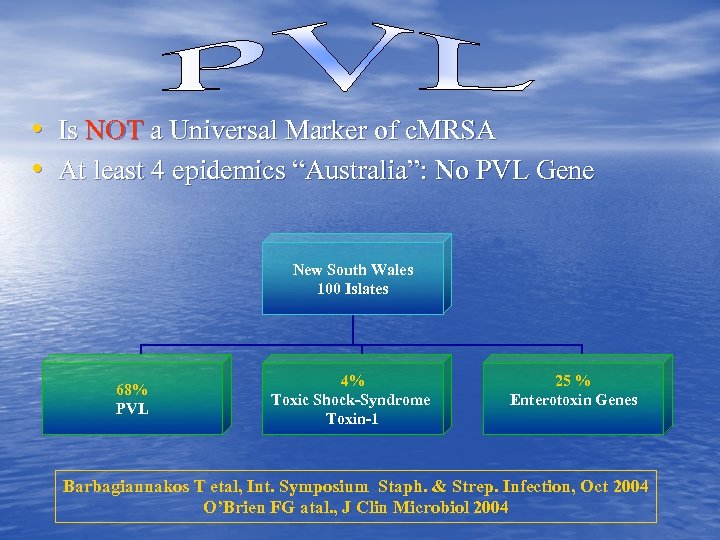

• Is NOT a Universal Marker of c. MRSA • At least 4 epidemics “Australia”: No PVL Gene New South Wales 100 Islates 68% PVL 4% Toxic Shock-Syndrome Toxin-1 25 % Enterotoxin Genes Barbagiannakos T etal, Int. Symposium Staph. & Strep. Infection, Oct 2004 O’Brien FG atal. , J Clin Microbiol 2004

• Is NOT a Universal Marker of c. MRSA • At least 4 epidemics “Australia”: No PVL Gene New South Wales 100 Islates 68% PVL 4% Toxic Shock-Syndrome Toxin-1 25 % Enterotoxin Genes Barbagiannakos T etal, Int. Symposium Staph. & Strep. Infection, Oct 2004 O’Brien FG atal. , J Clin Microbiol 2004